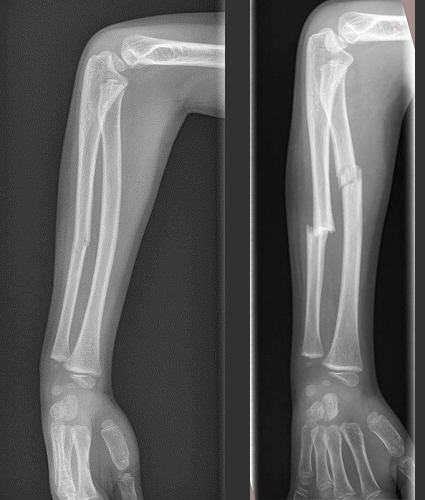

Nuestro paciente es un niño de 7 años al que, tras sufrir dos fracturas sin mecanismos de alto impacto, se le realiza una analítica para descartar causas de osteoporosis secundaria. En julio de 2021 presenta una fractura diafisaria de cúbito derecho sin desplazar que cura tras inmovilización con yeso cerrado braquiopalmar (Fig. 1). A principios de septiembre de 2021 sufre una fractura radiocubital diafisaria derecha tras caída desde su propia altura que precisa corrección quirúrgica (Fig. 1). En el control en el centro de salud se revisan radiografías impresionando de disminución de la masa ósea. La familia no refiere otra sintomatología y la exploración completa, incluyendo antropometría, es normal. No presentaba antecedentes familiares de patología tiroidea, celiaquía ni diabetes mellitus tipo I. Se realiza estudio analítico incluyendo hemograma, bioquímica básica, metabolismo fosfocálcico, vitamina D, metabolismo férrico, marcadores de inflamación, daño hepático y muscular, función tiroidea y anticuerpos antitransglutaminasa. En la analítica destacan unos anticuerpos antitransglutaminasa más de diez veces por encima del valor de referencia (8587,7 U/ml con límite de 20 U/ml). Al informar a la familia de estos hallazgos refieren que el paciente presentaba dolor abdominal intermitente y unas dos o tres deposiciones blandas diarias en las últimas dos o tres semanas. Ante la sospecha de una forma no clásica de EC es derivado al servicio de Gastroenterología Pediátrica de forma preferente, donde repiten analítica con marcadores serológicos (antitransglutaminasa de 8202,4 U/mL y antiendomisios positivos) y genéticos (HLA DQ2) que confirman la sospecha diagnóstica.

Figura 1. A la izquierda, fractura diafisaria de cúbito derecho (07/2021). A la derecha, fractura diafisaria de cúbito y radio derechos (09/2021)

Figura 1. A la izquierda, fractura diafisaria de cúbito derecho (07/2021). A la derecha, fractura diafisaria de cúbito y radio derechos (09/2021).